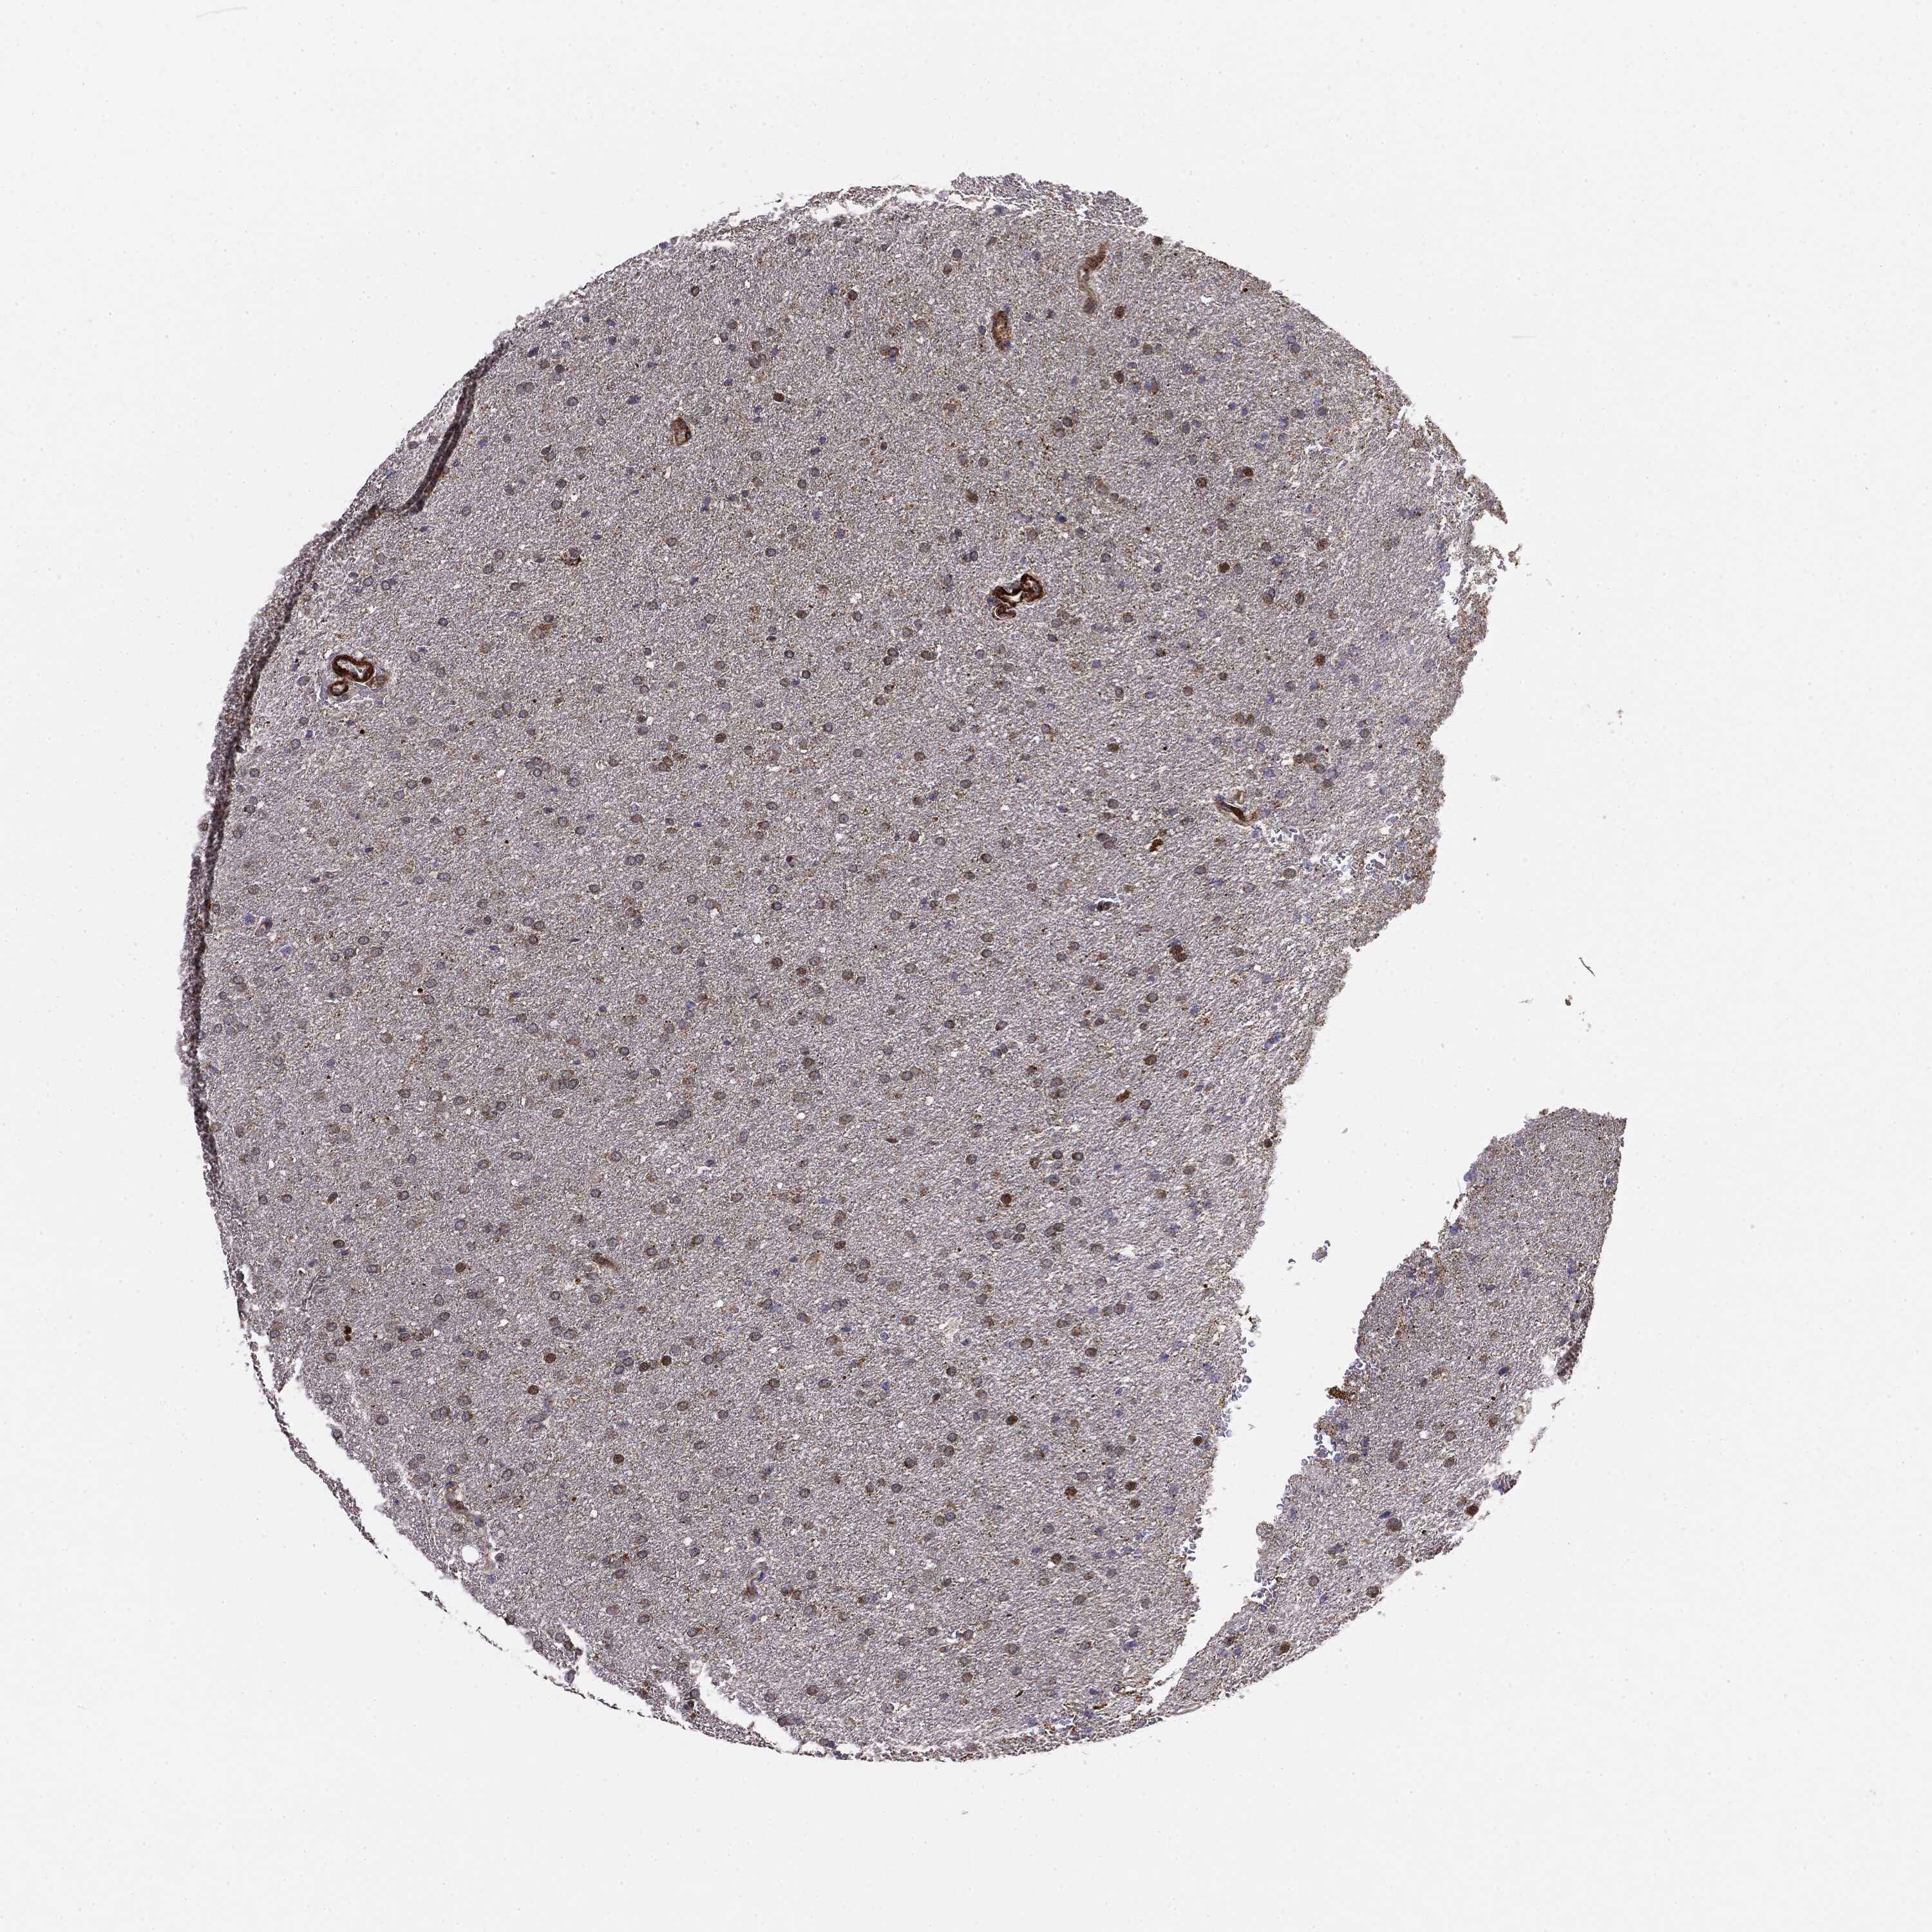

GLIOMA - Protein expressioni

A mouse-over function shows sample information and annotation data. Click on an image to view it in a full screen mode. Samples can be filtered based on level of antibody staining by selecting one or several of the following categories: high, medium, low and not detected. The assay and annotation is described here.

Note that samples used for immunohistochemistry by the Human Protein Atlas do not correspond to samples in the TCGA dataset.

Antibody stainingi

Antibody staining in the annotated cell types in the current human tissue is reported as not detected, low, medium, or high, based on conventional immunohistochemistry profiling in selected tissues. This score is based on the combination of the staining intensity and fraction of stained cells.

Each image is clickable and will lead to virtual microscopy that enables deeper exploration of all samples and also displays staining intensity scores, fraction scores and subcellular localization as well as patient and tissue information for each sample.

Antibody HPA031335

Antibody CAB004076

Antibody CAB080153

Antibody CAB080157

Glioma, malignant, Low grade

Glioma, malignant, High grade

Glioma, malignant, NOS